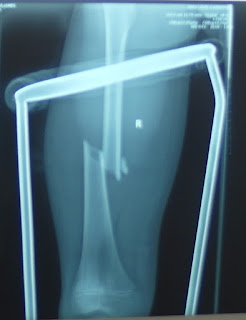

Visito rapidamente il piccolo, e non mi ci vuole molta scienza per comprendere che il femore sinistro e’ spezzato in due.

La madre insiste che si tratta invece del ginocchio, e non della coscia.

Continuiamo a dissentire per un po’, ed alla fine devo ricorrere ad un metodo un po’ rude per convincerla: le metto una mano su quello che io penso sia il focolaio di frattura; poi premo la sua mano con la destra, mentre la mia sinistra solleva lentamente il piedino di Amos, che strilla in un attimo di dolore intensissimo.

La donna ritrae l’arto con una smorfia di orrore; ha avvertito lo scroscio dei monconi ossei che andavano in collisione.

E’ tardi ma posso mettere una doccia gessata che certamente permetterà al piccolo di non avere dolore e di dormire bene.

Lo metteremo in lista domattina.